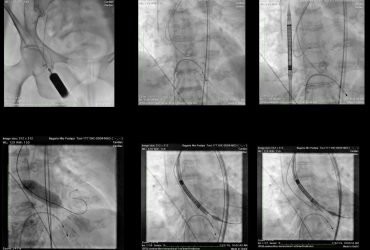

- The previous stent in the graft was cut open

- A new stent was precisely placed

- The 99% blockage was fully opened

- IVUS (Intravascular Ultrasound) confirmed perfect stent expansion and positioning

- Full blood flow to the heart was restored